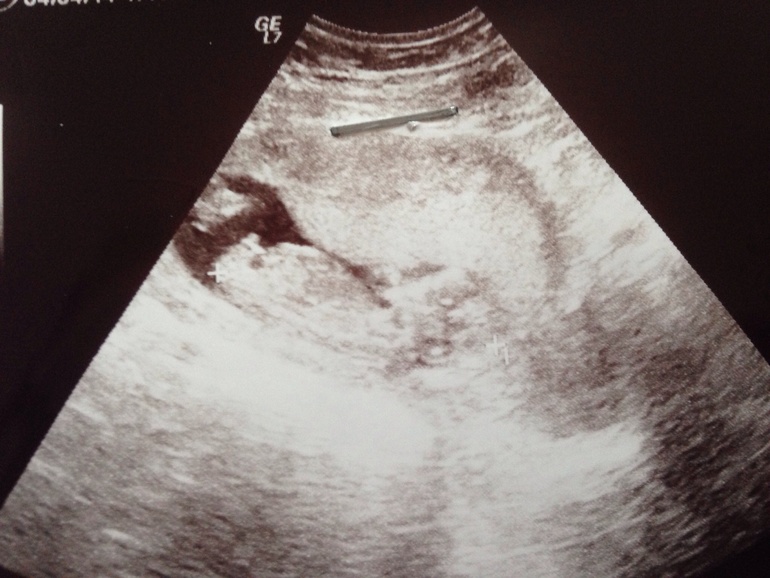

Прям 200??я боюсь как бы за 3 недели ни чего отвалилось))нам все равно но просто сказали мальчик,а я давно мечтала о нем,но не надеялась))у нас одни бабы))

У меня в дневнике есть полезная ссылка на сайт про пол)но чтобы ты не искала,вот тебе сайт http://www.budumamoi.ru/uzi_development.html там прям на картинках все про половые бугорки написано)

О я в этих бугарках не поняла,спросила врача она намекнула что на та ком сроке уже не по нему смотрят))короче ни фига не поняла))